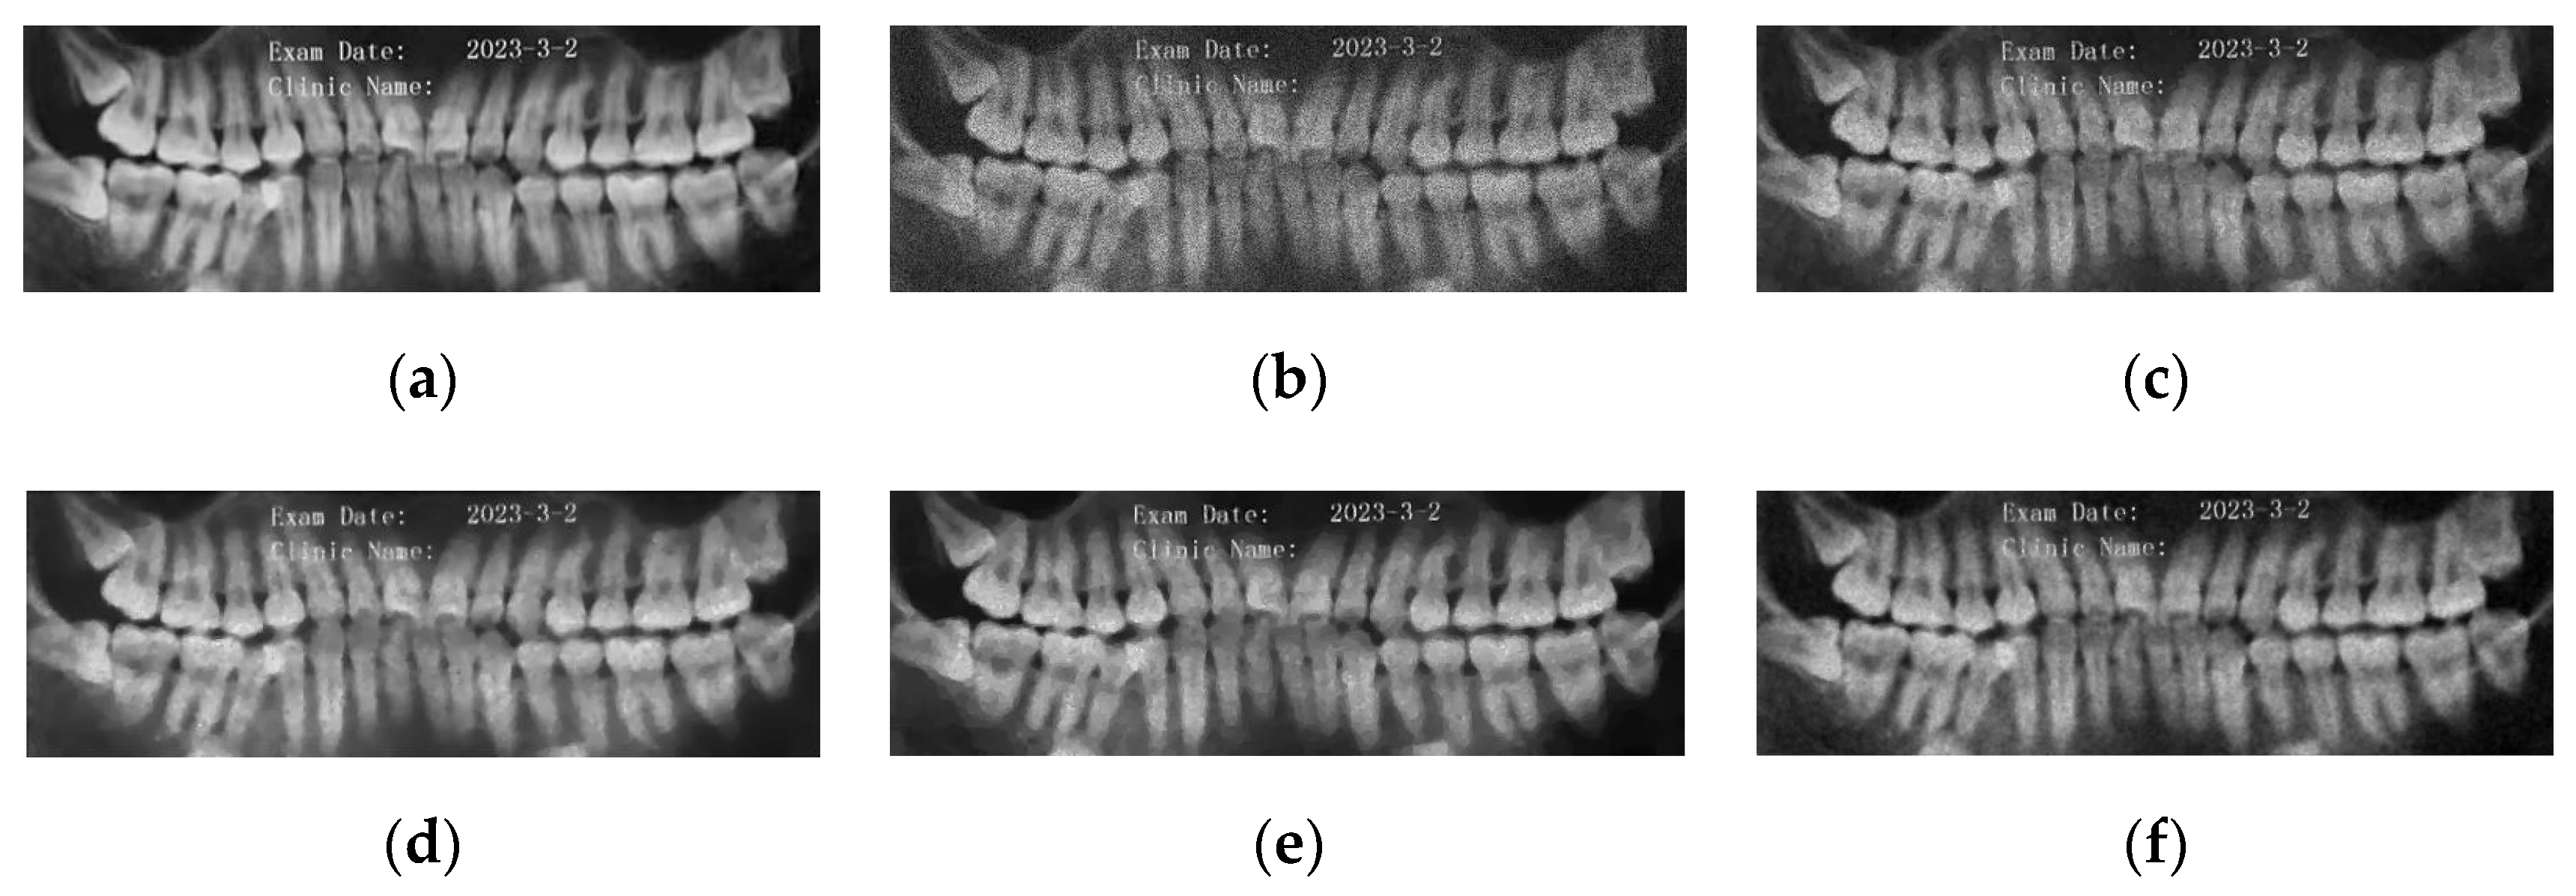

5.2. Numerical Simulations on Medical Images

5.2.2. Different Methods

- Partial Differential Equation Method

- ADMM Method

5.2.3. Comparison with Other Variational Models